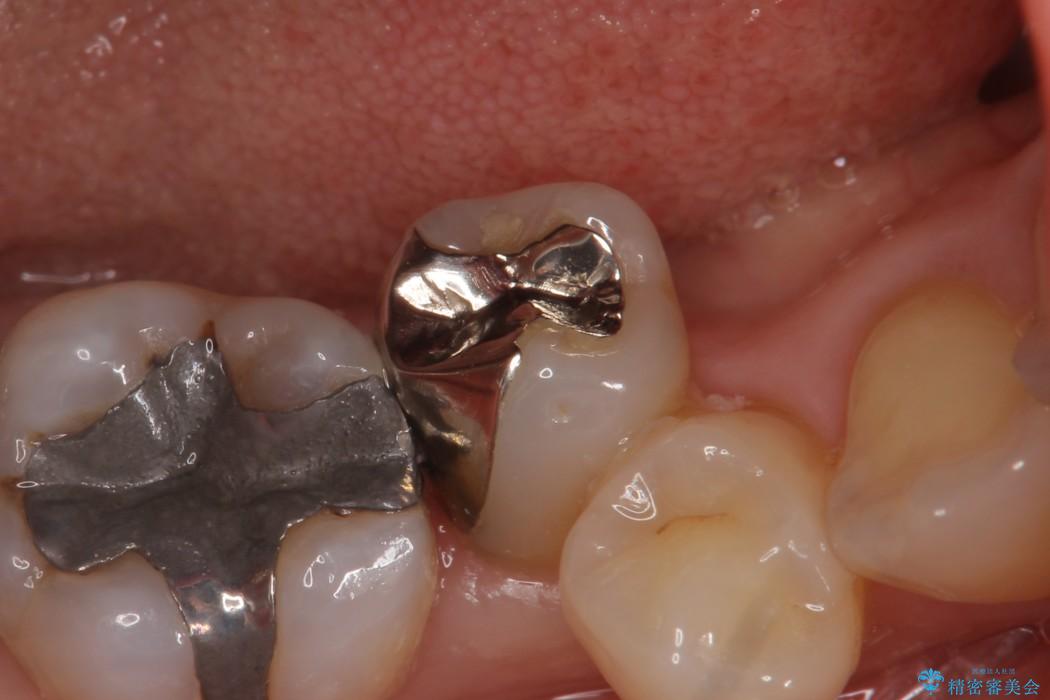

前の銀歯のように目立たず見た目のきれいな仕上がりとなり、大変喜んでいただきました。

また、セラミックは噛み合わせの力が強い場合などに割れる可能性があるため、しっかりと咬合調整を行い、無理な力が加わらないように仕上げます。